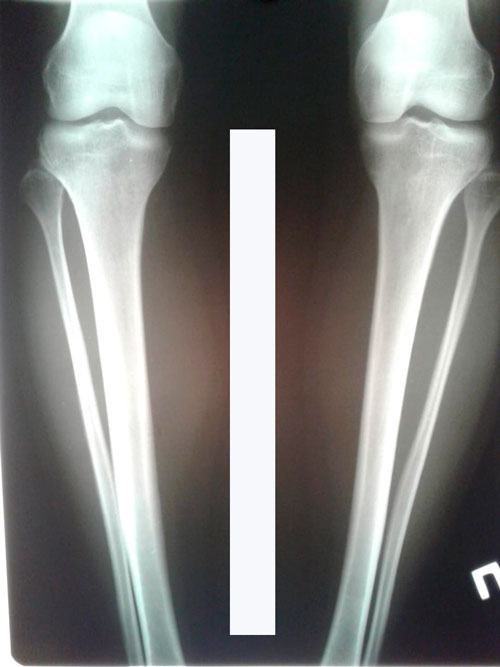

Исходник - 34 года.

Дата операции 31.07.2018г.

О - образная деформация обеих голеней, двойная Ротация.

Дата снятия аппаратов - 19.10.2018г.

Срок лечения - 78 дней.